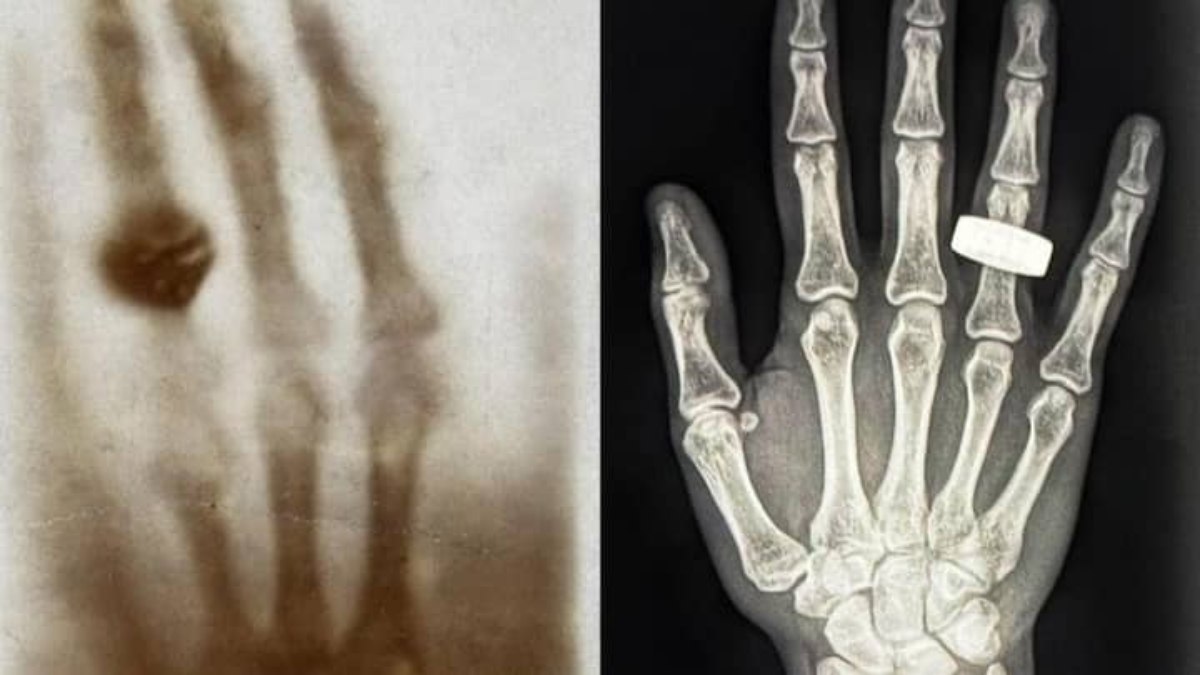

Astronotlar uzayda llk röntgeni çekti: Peki bu neden önemli